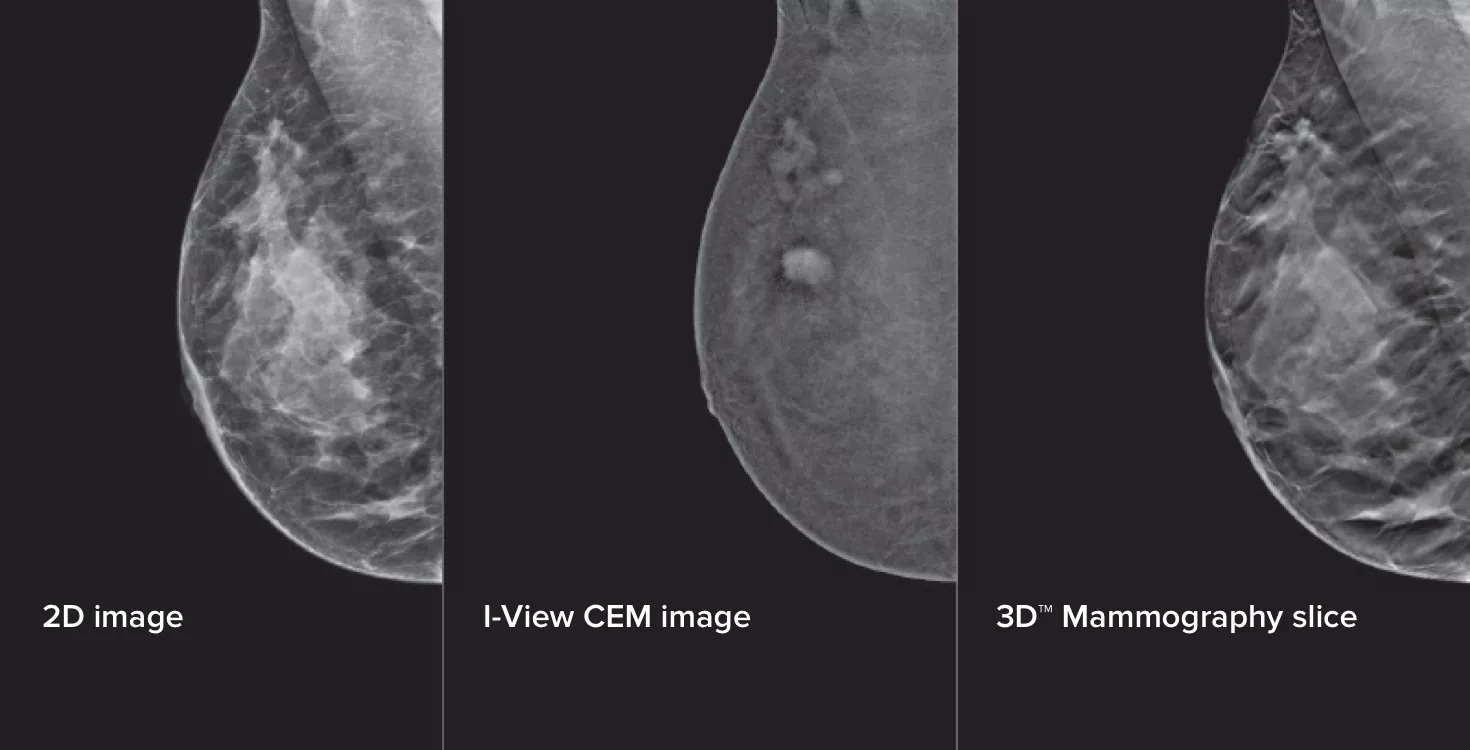

Contrast Enhanced Mammography (CEM), the imaging of a breast using iodinated contrast to reveal areas of increased blood supply within the breast, can help enhance suspicious lesions. The I-View software can combine the power of CEM with 2D and tomosynthesis images, all under one compression, providing anatomical and functional imaging in one exam.1

3 Images from 1 Compression

This software captures both anatomical and functional information in a single exam by leveraging our ability to provide 2D, contrast and tomosynthesis images in just one compression.1